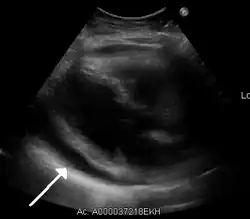

-

Ultrasounds showing a pericardial effusion in someone with pericarditis

The diagnosis of tamponade can be confirmed with trans-thoracic echocardiography (TTE), which should show a large pericardial effusion and diastolic collapse of the right ventricle and right atrium. Chest X-ray usually shows an enlarged cardiac silhouette ("water bottle" appearance) and clear lungs. Pulmonary congestion is typically not seen because equalization of diastolic pressures constrains the pulmonary capillary wedge pressure to the intra-pericardial pressure (and all other diastolic pressures).